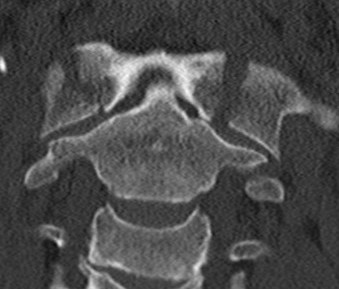

Type 2.  Posterior AND anterior arch fractures (Jefferson)

- axial compression

- +/- transverse atlantal ligament injury

JeffersonJeff illustration 1Jefferson illustration 2

2.  C1/C2 ratio

Lin et al Medicine 2019

- C1/C2 ratio > 1.1 80% sensitive of TAL injury

- C1/C2 ratio > 1.15 100% specific of TAL injury

C12 ratio 1C12 ratio 2